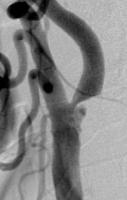

頸動脈ステント留置術

術前

狭くなり血流が悪くなってしまった頸動脈に、ステントと呼ばれる金属性のメッシュ状の筒を留置して血管を拡張させ、血流を回復させる手術です。